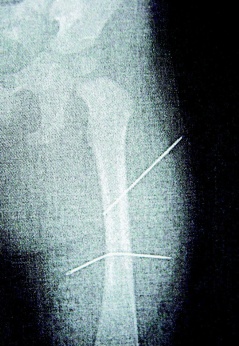

隔月27日,該女子又見外甥女哭鬧不停,拿蒼蠅拍朝著外甥女背部連打數(shù)十下,造成女娃背部瘀傷。經(jīng)女娃母親發(fā)現(xiàn)后送醫(yī)救護,院方為女童進行X光片照射后,才發(fā)現(xiàn)女娃左大腿里竟有兩根縫衣針。